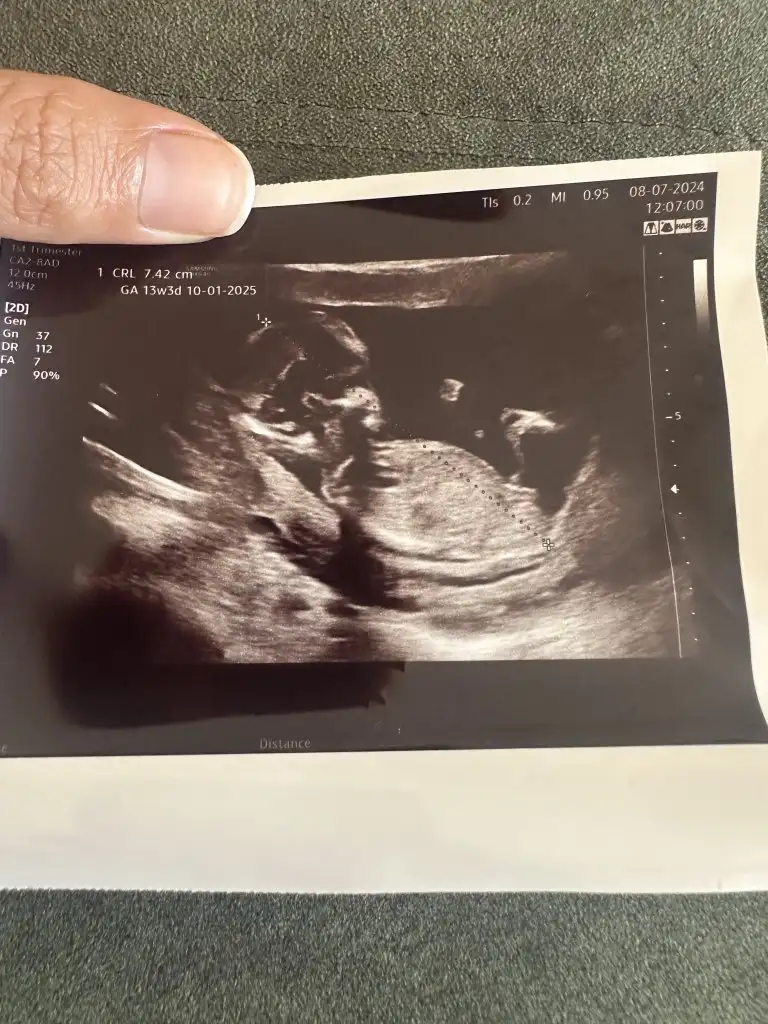

Hangi siteden baktırmıştınız acaba ?Ben Instagram dan baktırmıştım, tahminim %70 kız demişti, dün Dr %99 erkek dedi

Bugün gittim canım kız dedi doktorSanki çıkıntısı var erkek gibi duruyor

Ama çok erkek gibi duruyo yaBuda bugünün ultrasonu doktor kız dedi ama gören erkek diyor sizce ne